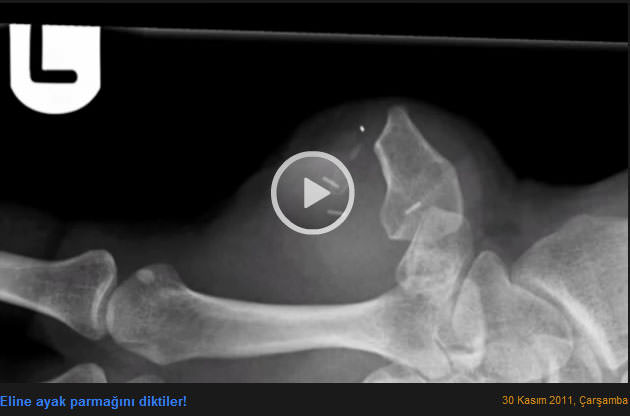

Eline ayak parmağını diktiler

İngiltere Bristol'da 29 yaşındaki marangoz James Byrne, geçtiğimiz Aralık ayında atelyede çalışırken, sol el baş parmağını kaybetti. Parmak işlevini yitirirken, genç marangoz defalarca ameliyat masasına yattı. Son operasyonda Byrne'nın sol ayak baş parmağı kesildi, kesilen ayak parmağı, sol eldeki baş parmağın yerine dikildi. Ayağında bir parmağını kaybeden adam, elindeki eksik parmağı tamamlayarak mesleğini yeniden yapma şansı buldu.